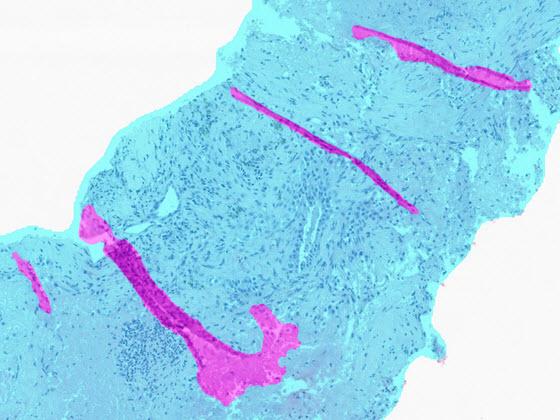

H&E slides depicting four types of digital pathology artifacts

SlideQC BF markup of four types of artifacts